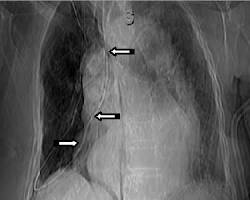

- Radyolojik Görüntüleme: En güvenilir yöntemdir. Özellikle uzun süreli kullanımlarda veya yerleşimden şüphe duyulduğunda akciğer grafisi ile sonda pozisyonu doğrulanmalıdır.